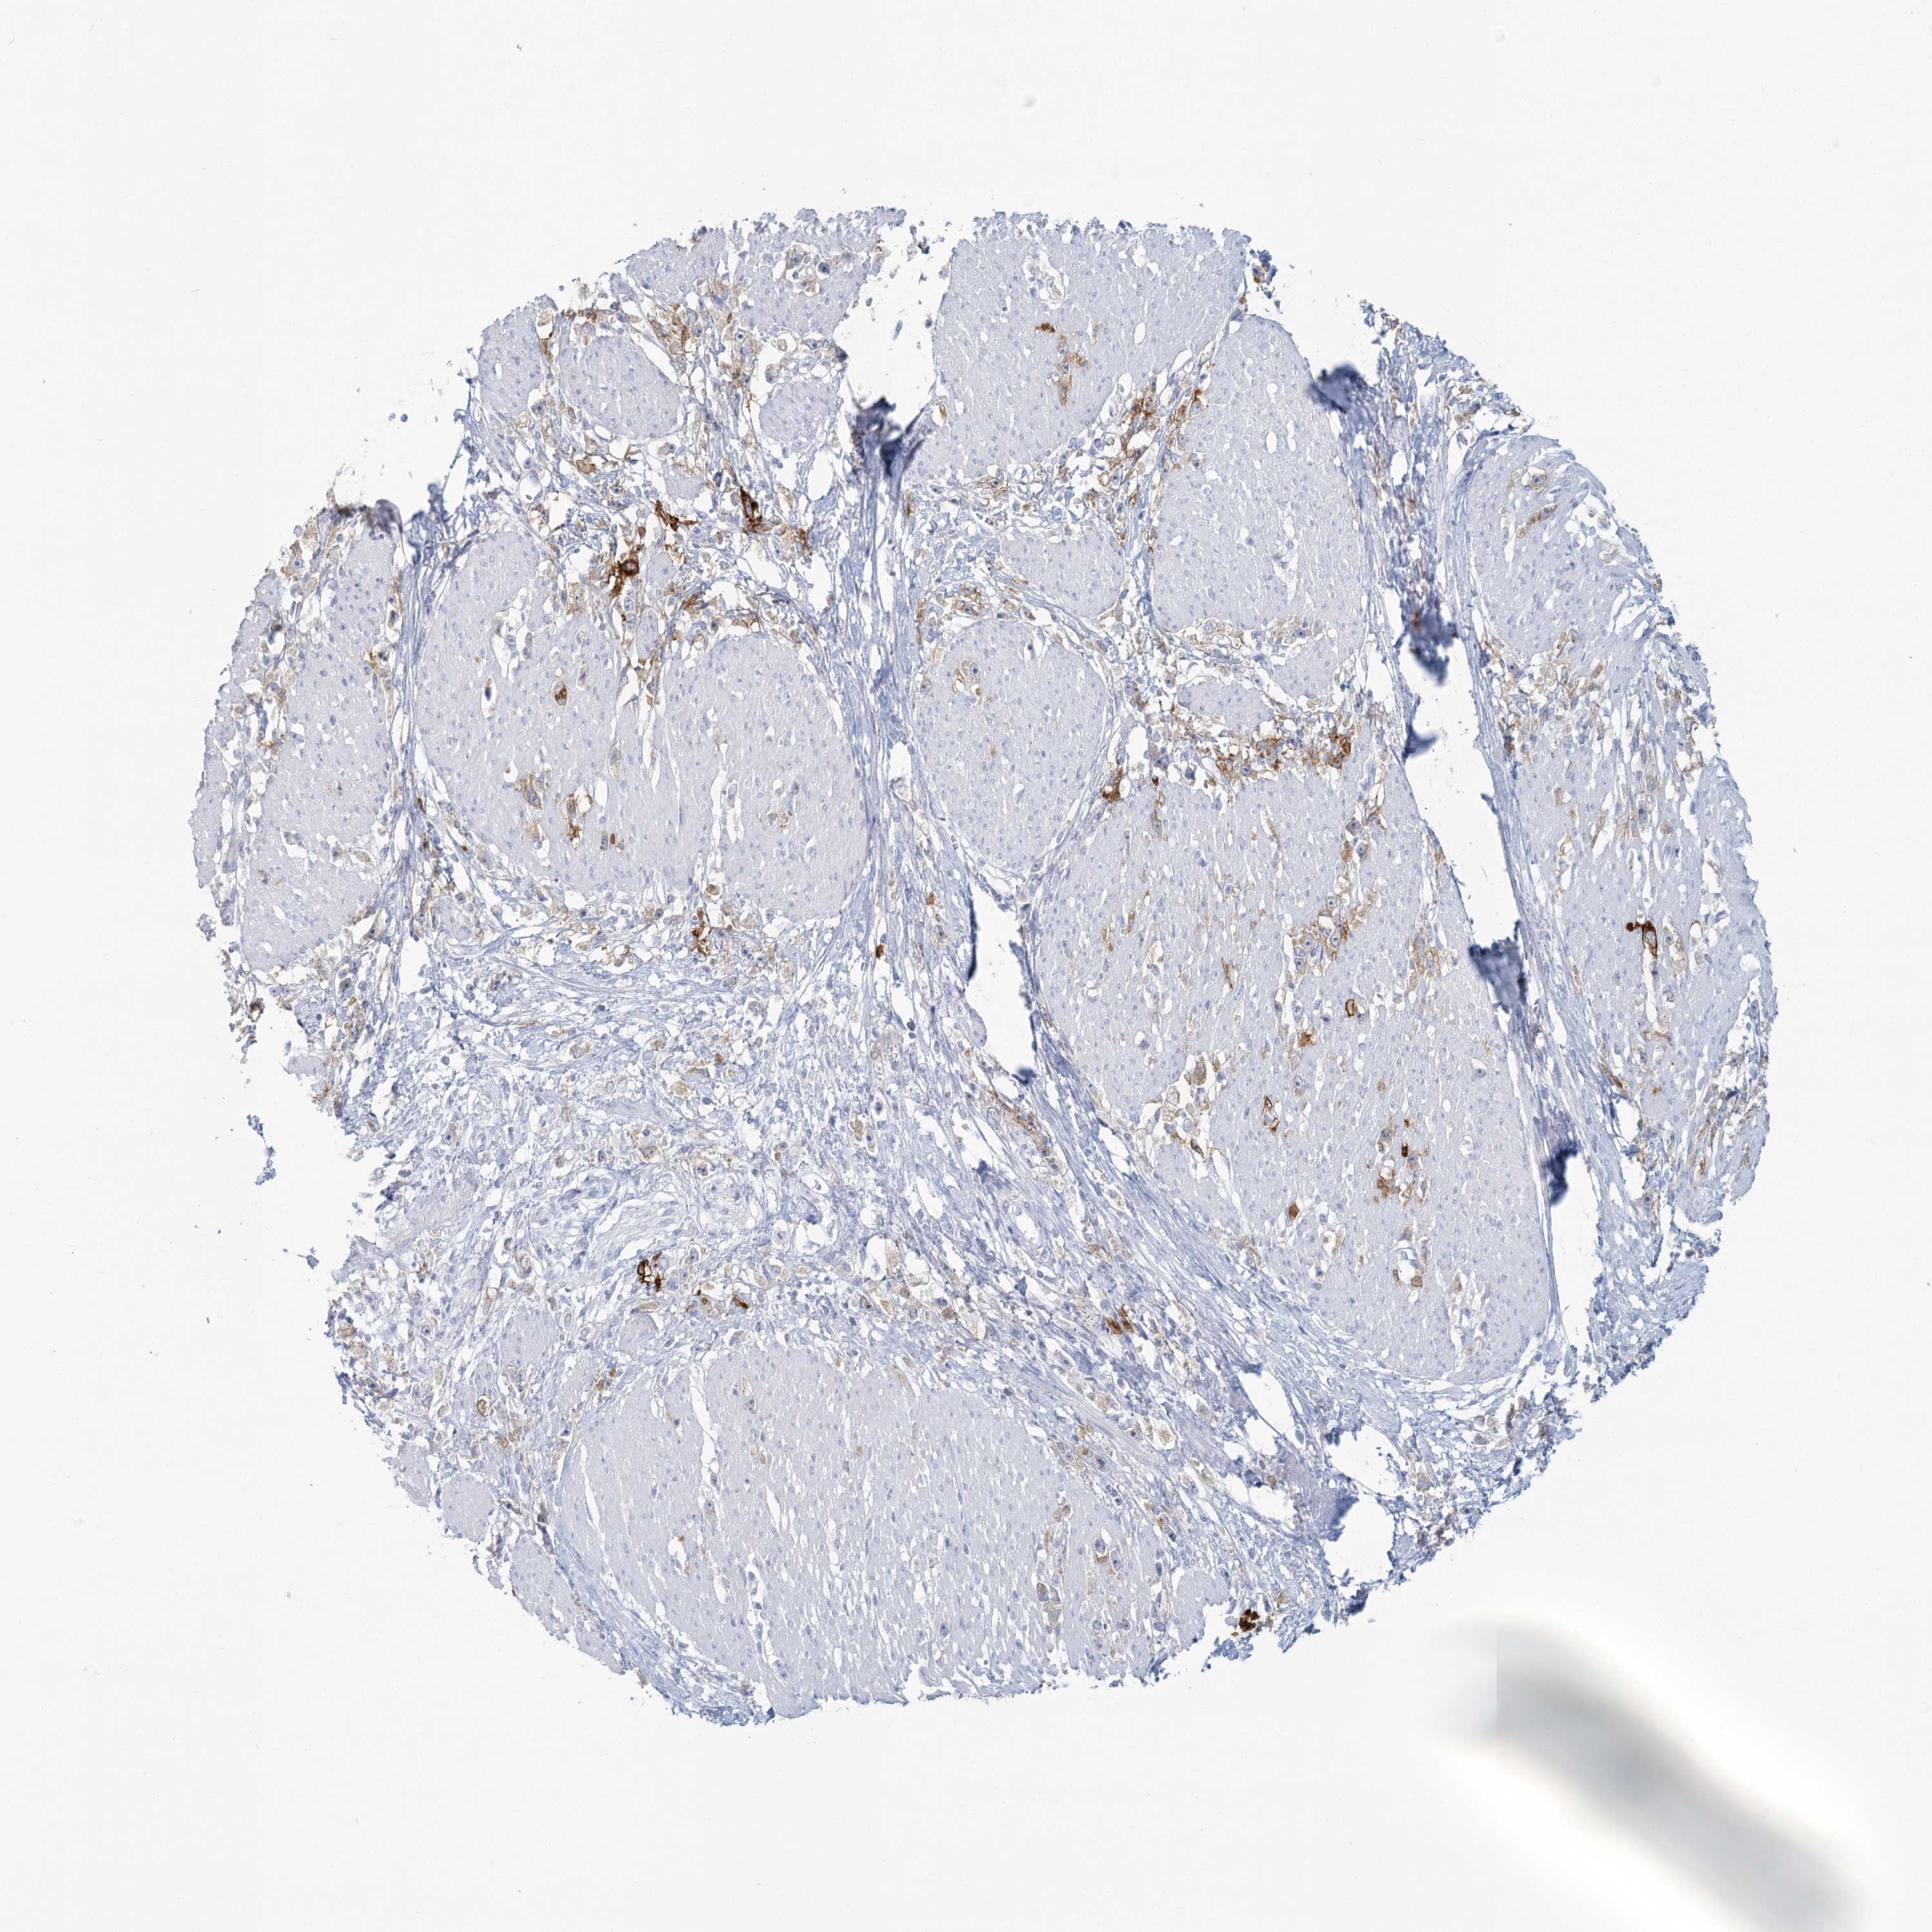

STOMACH CANCER - Protein expressioni

A mouse-over function shows sample information and annotation data. Click on an image to view it in a full screen mode. Samples can be filtered based on level of antibody staining by selecting one or several of the following categories: high, medium, low and not detected. The assay and annotation is described here.

Note that samples used for immunohistochemistry by the Human Protein Atlas do not correspond to samples in the TCGA dataset.

Antibody stainingi

Antibody staining in the annotated cell types in the current human tissue is reported as not detected, low, medium, or high, based on conventional immunohistochemistry profiling in selected tissues. This score is based on the combination of the staining intensity and fraction of stained cells.

Each image is clickable and will lead to virtual microscopy that enables deeper exploration of all samples and also displays staining intensity scores, fraction scores and subcellular localization as well as patient and tissue information for each sample.

Antibody HPA036752

Antibody HPA036753

Staining

High

Medium

Low

Not detected

Intensity

Strong

Moderate

Weak

Negative

Quantity

>75%

75%-25%

<25%

None

Location

Nuclear

Cytoplasmic/membranous

Cytoplasmic/membranous,nuclear

Adenocarcinoma, NOS